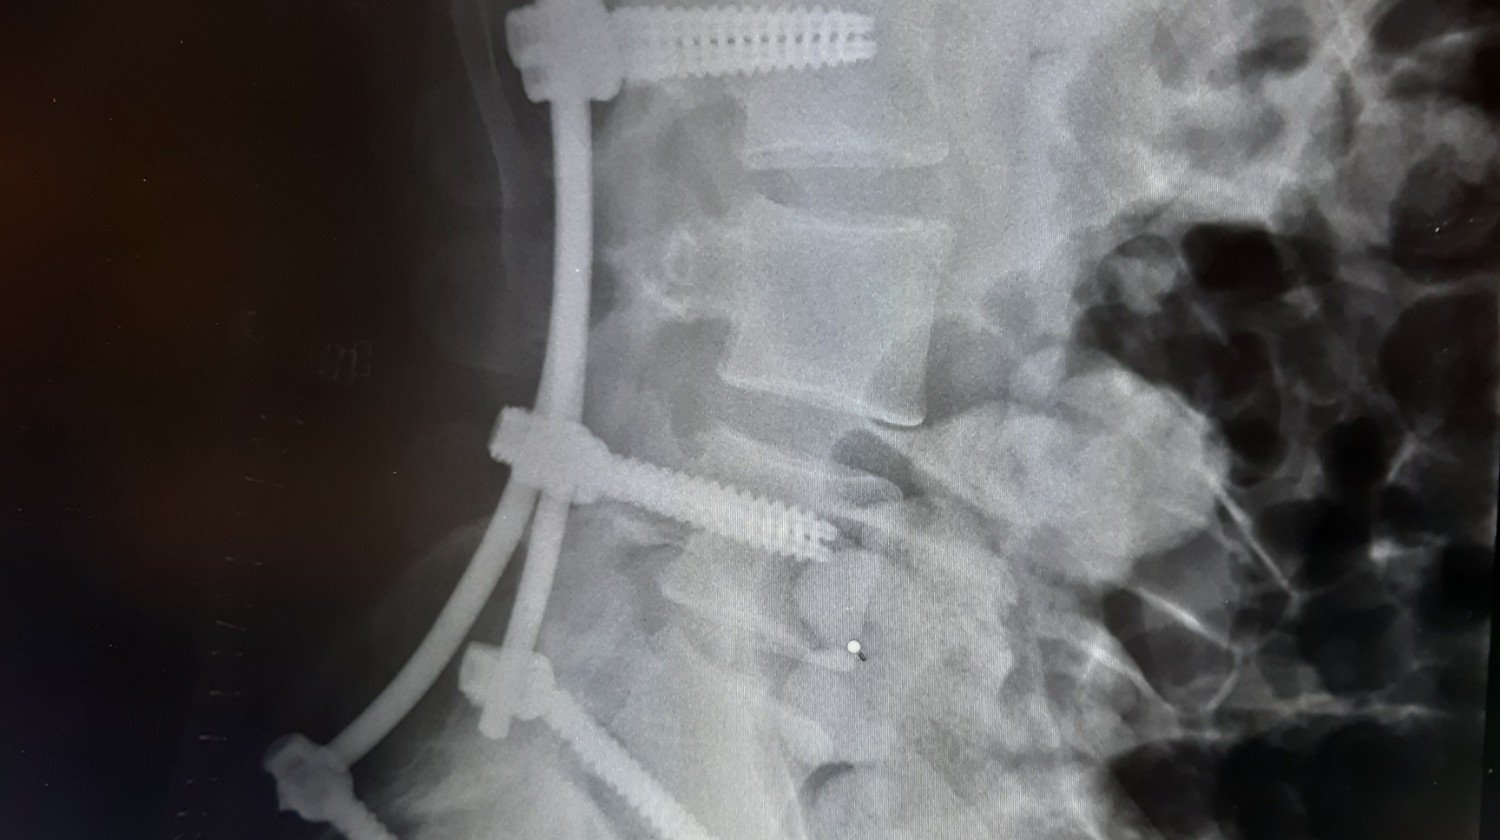

Po niedawnym wypadku moje życie zmieniło się drastycznie. Obrażenia uniemożliwiają mi normalne funkcjonowanie i powrót do zdrowia. Proszę o wsparcie finansowe na rehabilitację, która jest kluczowa dla mojego powrotu do sprawności. Każda wpłata będzie ogromną pomocą w mojej drodze do zdrowia. Dziękuję za każdą okazaną pomoc i wsparcie.